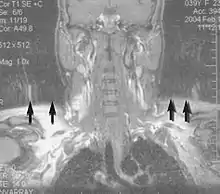

Neuroimaging

MRI is the investigative tool of choice for neurological cancers over CT, as it offers better visualization of the posterior cranial fossa, containing the brainstem and the cerebellum. The contrast provided between grey and white matter makes MRI the best choice for many conditions of the central nervous system, including demyelinating diseases, dementia, cerebrovascular disease, infectious diseases, Alzheimer's disease and epilepsy.[30][31][32] Since many images are taken milliseconds apart, it shows how the brain responds to different stimuli, enabling researchers to study both the functional and structural brain abnormalities in psychological disorders.[33] MRI also is used in guided stereotactic surgery and radiosurgery for treatment of intracranial tumors, arteriovenous malformations, and other surgically treatable conditions using a device known as the N-localizer.[34][35][36] New tools that implement artificial intelligence in healthcare have demonstrated higher image quality and morphometric analysis in neuroimaging with the application of a denoising system.[37]